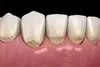

Elle se caractérise par une cavité située dans la partie cervicale de la dent, c’est-à-dire au niveau de la jonction entre la couronne et la racine. Cette lésion est brillante, dure au sondage et peut prendre une légère coloration brune.

Ce défaut de la dent n’est pas lié à une carie.